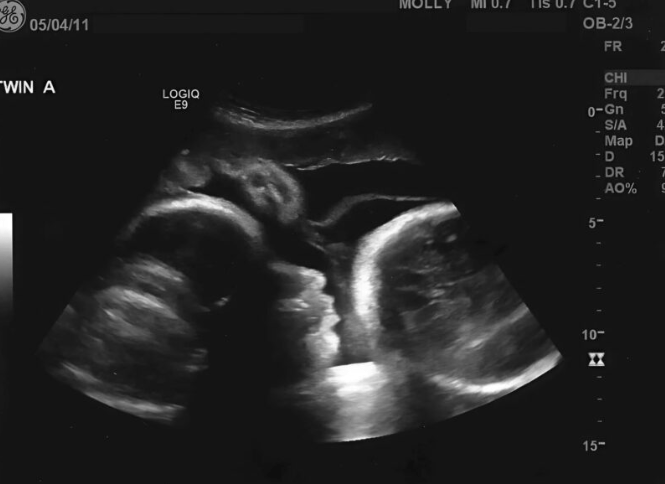

Doktor, iskusan i naviknut na razne situacije, pristupio je pregledu smireno i profesionalno. Ipak, već na početku bilo je jasno da nešto nije u redu. Nije bilo uobičajenih znakova trudnoće koje bi očekivao kod žene koja tvrdi da je u devetom mjesecu. Umjesto toga, ono što je otkrio izazvalo je šok.

Nakon detaljnog pregleda i dodatnih analiza, postalo je jasno da Larisa nije trudna. Ono što je osjećala nije bilo dijete, već stanje poznato kao lažna trudnoća, ili medicinski rečeno pseudocyesis. Ovo stanje može biti izuzetno snažno i uvjerljivo, jer tijelo i um zajedno stvaraju simptome koji oponašaju stvarnu trudnoću.

Kod Larise, simptomi su bili toliko izraženi da su uključivali i fizičke promjene, što je dodatno učvrstilo njeno uvjerenje. Međutim, iza svega se krila kompleksna kombinacija psiholoških i hormonalnih faktora.